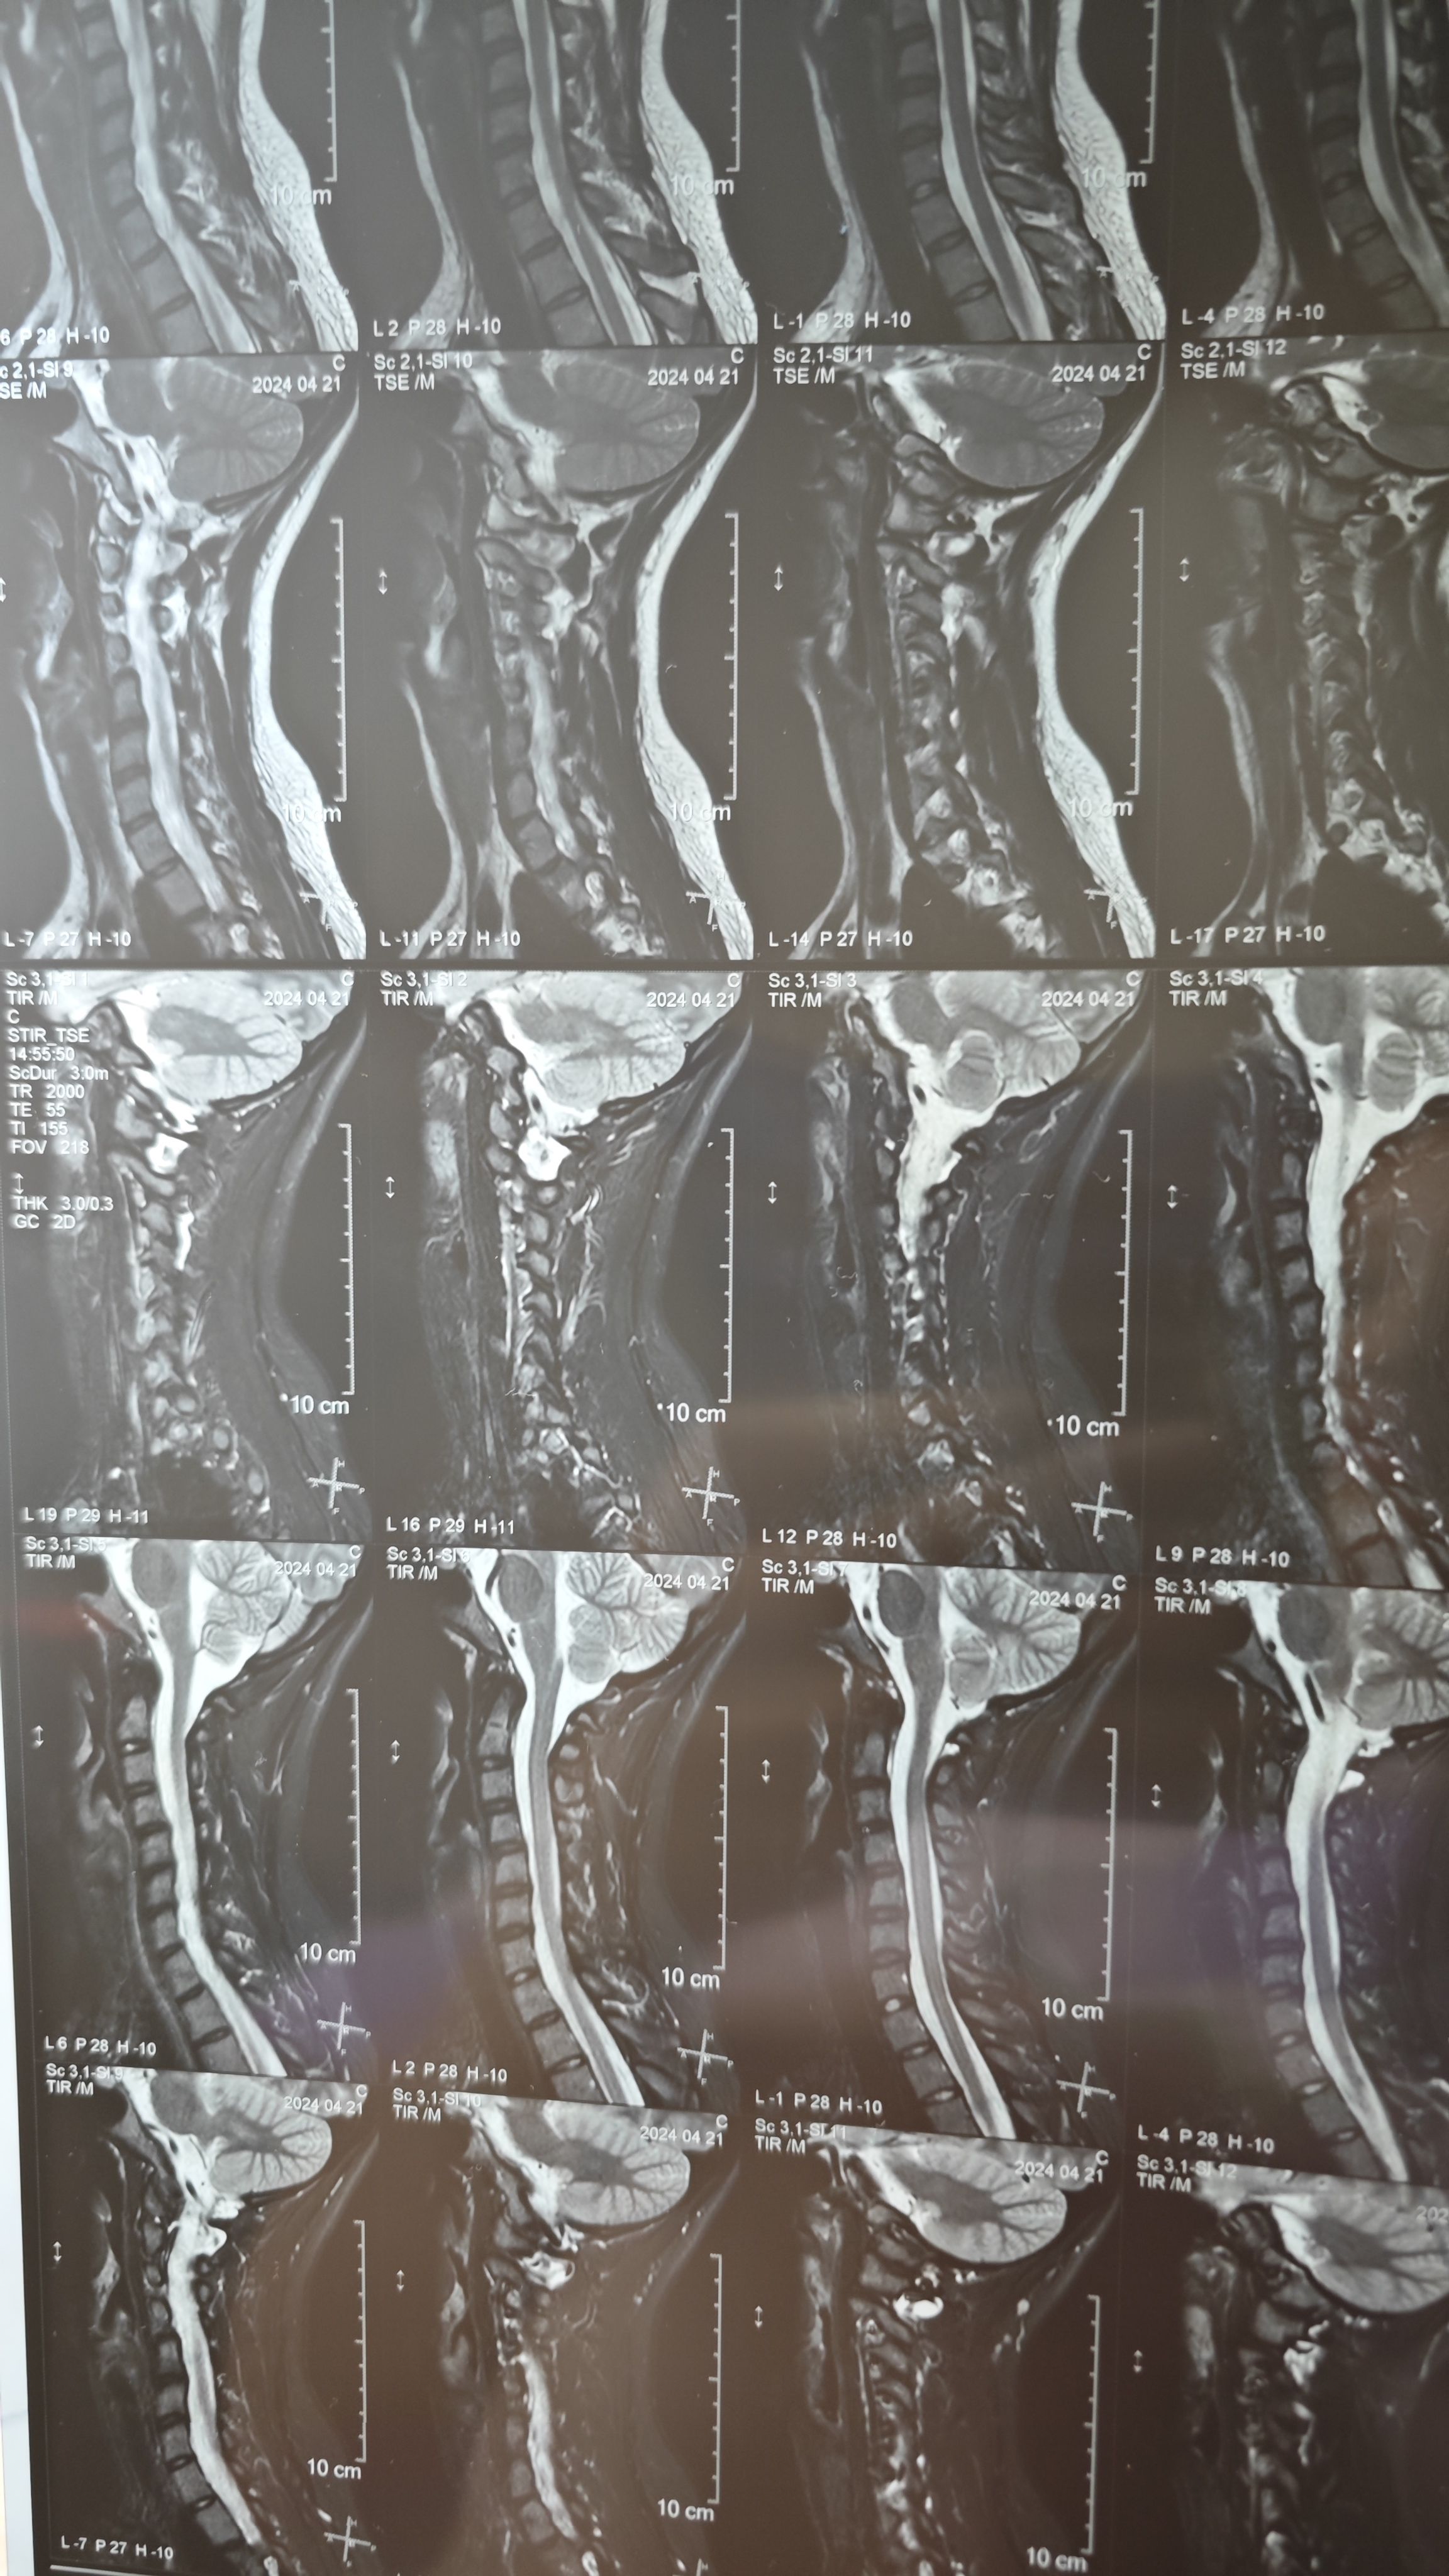

小肥在正骨推拿理疗科见习中,由于部分症状容易与其他病症混淆,或错误方式治疗,可能导致延误就医,故在此开串记录日常并穿插科普与治疗建议。

但请注意,小肥不提倡赛博就医,在这串里不会得到具体治疗方案与手法等细节,若肥哥卿姐有需要,可以将自己或亲友的病症,影象结果,治疗过程等按照以下格式发到本串,小肥会在咨询老师白嫖挂号费的情况下转达解答与建议(`・ω・)

串首是小肥岌岌可危但由于不影响正常生活故不用治疗的颈椎(; ゚ 3゚)

( ゚∀。)肥哥支持赛博康复运动推荐么,也不知道有没有见过我这样的病例,我先自述下病情,曲度变直确诊5年,从去年开始恶化,头部没有支撑就无法低头/长时间正坐,会产生无力抵抗的眩晕。前前后后跑过三家医院,都没能给出有效的治疗手段,不过最近几个月打有氧拳击感觉缓解了一丁点。之前病情不严重的时候隔几个月会去做一段时间正骨,现在这个样子也不敢动了( ゚∀。)肥哥我还有救么,还是认命比较好

你这个片子看起来对神经挤压还不是很严重,但是有点影响了已经,建议是去医院复查一个颈椎正侧位加开口位DR发上来,头晕的这个怀疑是寰枢寰齿关节这边有问题,复查个DR让我康康你的露骨照片( ゚ 3゚)